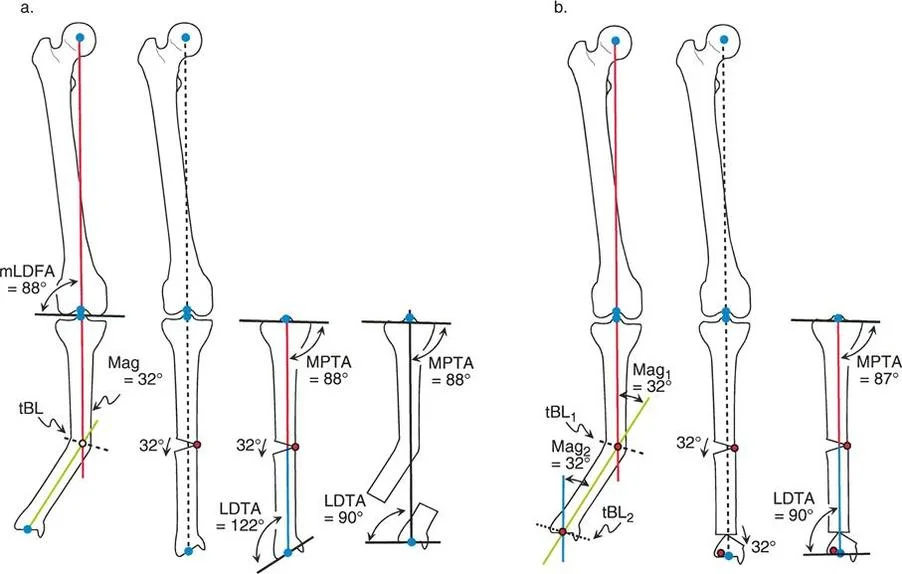

المحور الميكانيكي مقابل المحور التشريحي

لفهم التشوه، يجب على الجراحين تقييم أجزاء العظام الفردية:

- عظم الساق (الظنبوب): في عظم الساق، المحور الميكانيكي (خط من مركز الركبة إلى مركز الكاحل) والمحور التشريحي (خط يمتد في منتصف القناة النخاعية) متطابقان تقريبًا.

- عظم الفخذ: في عظم الفخذ، يختلفان كثيرًا. يمتد المحور الميكانيكي لعظم الفخذ من مركز رأس الفخذ إلى مركز الركبة. بينما يمتد المحور التشريحي من الحفرة الكمثرية أسفل القناة النخاعية إلى مركز الركبة. عادةً ما يشكل المحور التشريحي زاوية تتراوح بين 5° إلى 7° (بمتوسط 6°) مع المحور الميكانيكي لعظم الفخذ.

مبادئ بالي لاتجاه المفصل (Paley's Principles of Joint Orientation)

بعد تحديد محاذاة الطرف السفلي (MAD)، يجب على الجراح تقييم اتجاه المفاصل بشكل منهجي بالنسبة للمحور الميكانيكي. لكل مفصل ميل طبيعي يمكن التنبؤ به بدرجة عالية. تشكل هذه القيم الطبيعية الخطوط والزوايا المرجعية التي تُعد متطلبات أساسية للتخطيط قبل الجراحة ولتحديد مركز دوران الزاوية (CORA).

زوايا اتجاه المفصل القياسية (بالي):

| اختصار الزاوية | الاسم الكامل بالإنجليزية | القيمة الطبيعية | الأهمية السريرية |

|---|---|---|---|

| LPFA | Lateral Proximal Femoral Angle | 90° (89.9° ± 5.2°) | تقييم تقوس/فحج عظم الفخذ القريب (مثل جنف الورك). يوجه عمليات قطع عظم الفخذ القريب. |

| mLDFA | Mechanical Lateral Distal Femoral Angle | 88° (87.8° ± 1.6°) | يحدد خط المفصل لعظم الفخذ البعيد. حاسم لعمليات قطع عظم الفخذ البعيد (DFO) واستبدال مفصل الركبة الكلي (TKA). |

| MPTA | Medial Proximal Tibial Angle | 87° (87.2° ± 1.5°) | يحدد خط المفصل لعظم الساق القريب. المقياس الأساسي لعملية قطع عظم الساق العالية (HTO). |

| JLCA | Joint Line Convergence Angle | 0° - 2° | يقيم التشوه داخل المفصل، فقدان الغضروف، أو رخاوة الأربطة الجانبية. |